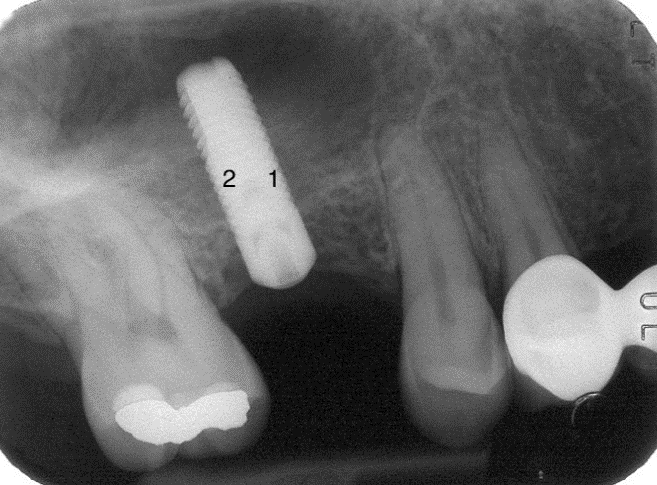

Rigenerazione mesiale 1: 5.4 mm

Rigenerazione distale 2: 4.2 mm*

Rigenerazione tratti intermedi 3: 6.4 mm

I versanti mesiali e distali presentano rigenerazioni leggermente minori a causa della spinta dell’aria causata dall’attività pneumica del seno mascellare

Cinque anni dopo gli stessi pazienti sono stati nuovamente valutati clinicamente e radiograficamente. Tutti gli impianti risultarono stabili ed asintomatici. La perdita di osso marginale che ad un anno si era rivelata di una media di 0,36mm, dopo cinque anni si è dimostrata essere di 0,7 mm ovvero inferiori ai valori di riassorbimento consentiti di 0,2 mm per ogni anno di carico.